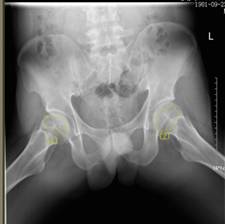

術前報告顯示患者雙側(cè)股骨頭壞死

37歲的患者吳先生反復雙髖疼痛2月余,聽說瀘州市中醫(yī)院在治療骨科疾病方面很有經(jīng)驗,遂來到醫(yī)院治療。經(jīng)檢查,吳先生雙側(cè)股骨頭壞死(II期),如不及時進行手術治療,他的股骨頭將進一步壞死至骨頭塌陷,引發(fā)關節(jié)炎,嚴重時,必須行關節(jié)置換術。這樣,將會給吳先生的生活質(zhì)量及經(jīng)濟帶來嚴重負擔。